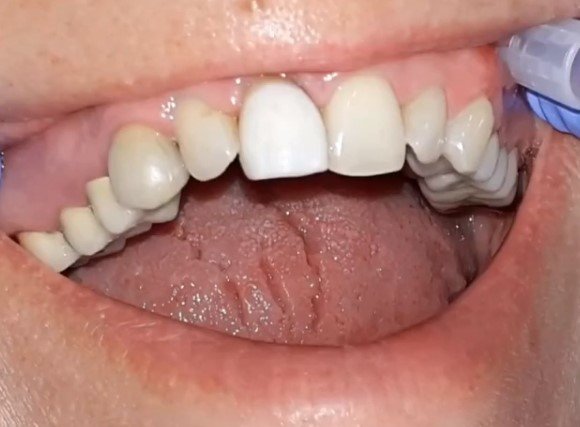

Фронтальные зубы как никогда важны для пациента! Конечно работа с передними зубами сложна и кропотлива! Требует особой тактики ведения. @dr.logvinov...